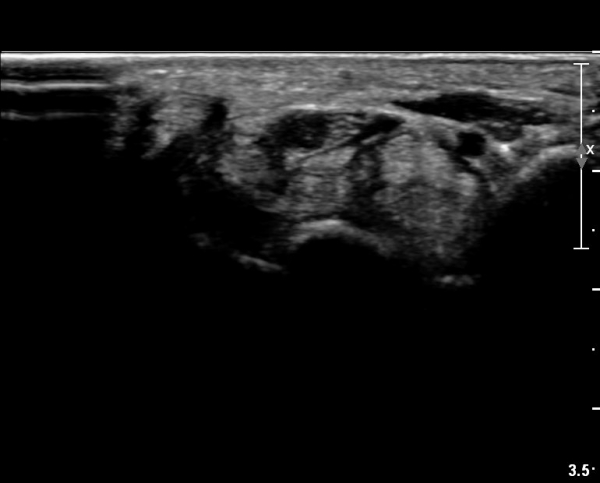

Å½ÃËÀÚ¸¦ ¸»´ÜÀ¸·Î À̵¿ÇÏÀÚ  Á¤Áß½Å굥 ¿äÃø ÀϺΰ¡ Àú¿¡ÄÚ Á¾±«·Î °üÂûµÊ(»çÁø 2).

ÀÌ·± ¸ð½ÀÀº ¼Õ¸ñÀÇ ¿ù»ó°ñ ºÎÀ§(»çÁø 3, 4)¸¦ Áö³ª ¼ö±Ù°ü ±ÙÀ§ºÎ ±îÁö À̾îÁü(»çÁø 5).